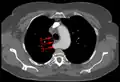

Aberrant subclavian artery at axial CT-scan. (1) trachea, (2) esophagus, (3) aberrant subclavian artery. -